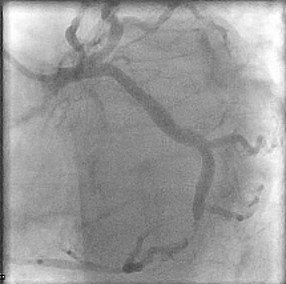

Patient was informed of these high-risk findings on CCTA with evidence of obstructive CAD and the decision was made to proceed with the gold standard left heart catheterization with coronary angiography to ensure accuracy of the obstructive lesion and intervention if the lesion was found to be obstructive. Cardiac catheterization revealed an obstructive lesion of the mid LCx with 80% calcified stenosis and he underwent successful Intravascular Ultrasound (IVUS) guided PCI of the LCx with pre and post balloon angioplasty utilizing a 3.5x22 and 3.0x15 mm overlapping Onyx frontier Drug-Eluting Stent (DES). LAD lesion angiographically appeared to be non-obstructive and medical management was elected (Figures 2-4).

Figure 2: Coronary angiography showing mid LCx obstructive lesion.